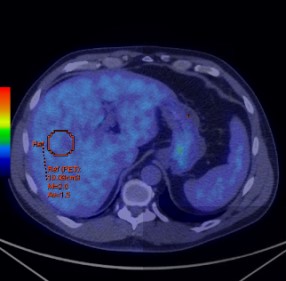

三、基于功能分子影像技术对肿瘤治疗疗效评价 从Moertel等在1976年报告基于体检方法对实体瘤治疗疗效评价,到WHO实体瘤治疗疗效评价标准(1979年),再发展到RECIST(2000)、RECIST1.1实体瘤治疗疗效评价标准。这些均是基于肿瘤解剖结构变化来评价治疗疗效。然而,许多年来已经有确切的证据表明,核医学分子影像技术可以提供独特的、生物学相关的、不可能通过解剖成像技术获得对肿瘤治疗预后的重要信息。有学者认为分子影像定量成像方法可以作为肿瘤疗效预测或治疗效果评价的生物学标志。 Yong等1999年发表采用18F-FDG PET 评价肿瘤治疗疗效的EORTC标准。该标准首次提出采用18F-FDG PET评价肿瘤治疗疗效。但是,该方法采用肿瘤病灶对18F-FDG 摄取率(standardized uptake value, SUV)作为评价肿瘤疗效指标。然而,采用体重校正的SUV存在重复性差、变异大,并且没有设置可观的参考本底的不足。另外,尽管该标准提出18F-FDG PET采集和图像处理的质量控制要求,但是缺乏严格的定量化的要求。随着PET/CT在临床广泛使用,以及EORTC在临床使用经验的积累。2009年Wahl Richard L在回顾WHO、RECIST实体瘤治疗疗效评价标准基础上,结合18F-FDG PET和PET/CT在肿瘤治疗效果预测和评价研究的大量数据后,提出实体瘤疗效PET评估标准1.0版本框架草案-PERCIST标准。PERCIST1.0标准建立在用PET评价肿瘤疗效是在连续的和不同时间点上监测肿瘤对18F-FDG摄取变化基础上。 (一) EORTC实体瘤治疗疗效评价 1. EORTC标准对肿瘤病灶基线期的定义 (1)可测量病灶与不可测量病灶的定义: 1)评价参数的确定:使用PET设备。可测量的病灶是指单个摄取18F-FDG的病灶。病灶对18F-FDG摄取测量采用病灶感兴趣区(ROI区)SUV或MRglu。选择肿瘤具有摄取最高18F-FDG摄取区域,在治疗前扫描中勾画ROI。 2)肿瘤病灶基线确定:参照肿瘤诊断的标准。 2. EORTC标准对肿瘤疗效评价 (1)靶病灶的疗效评价 CMR:肿瘤内的18F-FDG完全消失至不能与周围正常组织鉴别。 PMR:一个肿瘤化疗疗程后肿瘤18F-FDG SUV摄取至少降低15%-25%,一个疗程以上降低>25%;PMR并不要求肿瘤摄取18F-FDG范围缩小。 PMD:在基线扫描确定的肿瘤区域肿瘤18F-FDG SUV增加>25%;肿瘤18F-FDG摄取范围可见增加(最大长轴20%)或表现新的18F-FDG摄取灶。 SMD:病灶18F-FDG SUV增加<25%,或降低<15%,或未发现肿瘤18F-FDG摄取范围增加(最大长轴20%)。 (二)PERCIST1.0标准草案 1. PERCIST1.0标准草案对肿瘤病灶基线期的定义 (1)可测量病灶与不可测量病灶的定义: 1)评价参数的确定:可测量的病灶是指单个摄取18F-FDG的病灶。病灶对18F-FDG摄取测量采用病灶感兴趣区域(ROI)峰值替代传统的最大值或平均值。峰值是在1.2厘米直径球体内获得1厘米3最高值。采用SUL(Lean Body Mass)取代传统的SUV。 2)肿瘤病灶基线确定:按照肿瘤病灶的SUL峰值应当是1.5´肝脏平均SUL+2倍标准差。如果肝脏有疾病,那么肿瘤病灶最小有代谢可测量肿瘤的活性可以看作2.0´血池活性+2倍纵隔标准差。 3)肝脏和血池本底选择:在肝脏右下叶勾画3厘米ROI作为本底区(不能包含大血管组织)(见图2)。假如肝脏异常,原发肿瘤摄取应当>2.0 ´SUL (在降主动脉)。

图2 在肝脏勾画本底ROI示意图 4)不可以测量的病灶是指并未摄取18F-FDG病灶。 (2)靶病灶和非靶病灶: 当存在多个可以测量的病灶时,按照病灶大小及可以重复测量的原则,每个脏器最多选取2个病灶,总共不超过5个病灶作为靶病灶。靶病灶以外的所有病灶被看作为非靶病灶。 2、PERCIST标准对肿瘤疗效评价 (1)靶病灶的疗效评价 CMR:在可测量的靶病灶18F-FDG摄取完全消失以至于低于肝脏平均放射活性,并且不能与血池本底相区别。所有其它病灶消失至血池本底水平。在可以测量区域SUL降低应该记录,治疗开始后的时间也应该记录(比如,CMR -90,4)。假如RECIST是进展疾病,应该通过随访来验证。 PMR:在可测量靶肿瘤18F-FDG SUL峰值降低至少30%。最好,SUL绝对值下降到至少是0.8 SUL单位。测量通常是在同一病变作为基准,但也可以是不同病变。如果病变以前存在,治疗后是目前最活跃的病变。对于PMR并不要求肿瘤18F-FDG摄取范围减少。SUL降低的百分数应该记录,还有治疗开始后时间(周)(比如,PMR -40,3)。并没有新的病灶出现。 PMD:18F-FDG SUL峰值增加30%,并且与基准扫描相比,肿瘤峰值SUV增加大于0.8SUL单位,该肿瘤具备典型肿瘤模式,没有炎症或治疗效应。或者:18F-FDG肿瘤摄取可见范围扩大(TLG体积75% ,SUL没有降低)。SMD:不是CMR、PMR或PMD,在代谢目标病灶SUL峰值应该被记录,还应该有最近开始治疗的时间(周)(例如,SMD -15, 7)。 (2)非靶病灶疗效评价 CMR:所有18F-FDG病灶消失。 PMD:18F-FDG非目标病灶明显进展或典型肿瘤18F-FDG摄取呈现新的病灶。 SMD:即不满足CMR,又不是PMD。 3、PERCIST 1.0与EORTC标准的比较 表3是PERCIST 1.0与EORTC标准比较。可以看出EORTC和PERCIST1.0标准在肿瘤基线确定、评价参数的选择、以及疗效评价均存在明显的不同。PERCIST1.0是建立在PET/CT基础之上,强调在严格规范使用18F-FDG PET/CT前提下从定量化角度来评价肿瘤治疗疗效。 表3 PERCIST 1.0与EORTC比较 特征 | EORTC | PERCIST1.0 | 在基线可测量病变 | 肿瘤对18F-FDG摄取采用SUV | 采用ROI峰值和SUL。并且对病灶的选择按照参考值进行。需要计算TLG。规定靶器官病灶选择的总数目。 | 摄取归一化 | 扫描仪应该提供数据的重复性。 | 正常肝脏SUL应该是在20%(并且0.3SUL平均单位)作为基线和后续研究研究评价疗效。 | 客观疗效 | PMR、PMD均采用相对变化。 | 在PMR、PMD中进入SUL绝对单位量,并且强调需要记录从化疗开始到显像的时间。在PMR中采用TLG。 对非靶病灶具有明确的规定 | 总体疗效 | - | 最佳总疗效是指可测量病灶从治疗开始到疾病进展或复发之间所测量的最小值。 可测量肿瘤或不可测量非靶病灶非-PMD从CR退到总体PMR。 非靶病灶非-PMD并未退到PR。 | 总缓解期 | - | 总CMR:从治疗后首次评价为CMR时直至经评价为疾病复发获进展时间。 总体疗效:从治疗后经首次评价为CMR或PMR时直至评价为疾病复发或进展时间。须注意,CMR或PMR应在首次评价为CMR或PMR的4周后确认才能被认为是有效的。 SMD:从治疗开始到首次被确定为PMD时间。 |